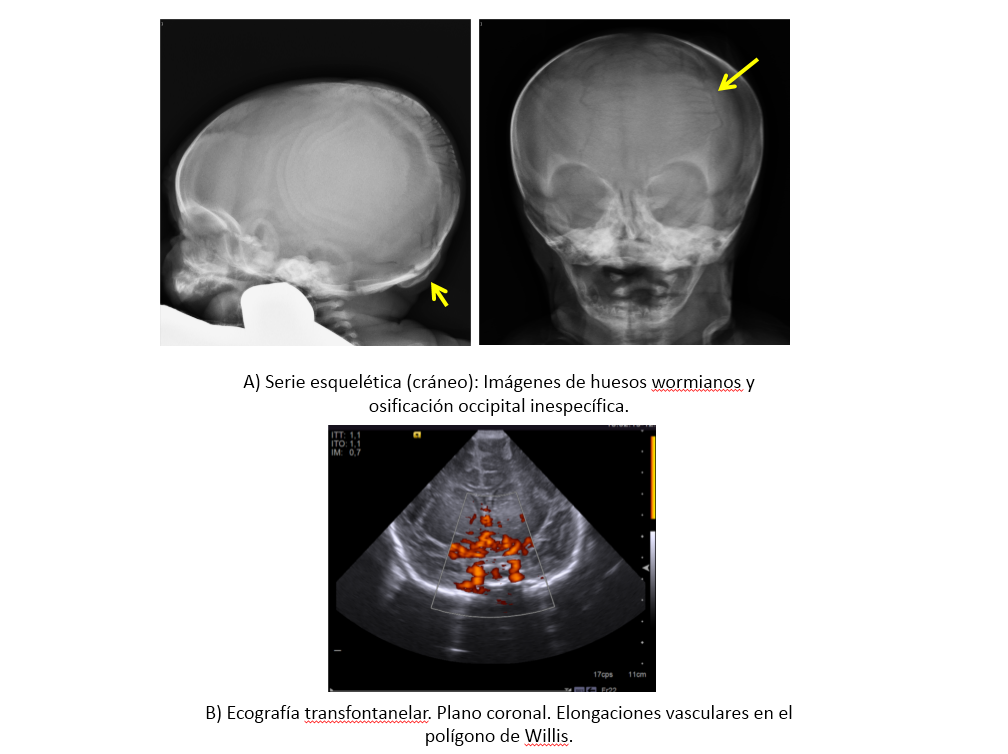

Hallazgos radiológicos: En el cráneo, se aprecian huesos wormianos y en huesos largos, ensanchamiento de las metáfisis, exóstosis y reacción perióstica. En cuanto a los hallazgos en SNC, se puede observar pérdida del volumen cerebral, colecciones subdurales y son característicos los vasos tortuosos y dilatados. En casos avanzados también se puede ver afectación de los ganglios de la base.